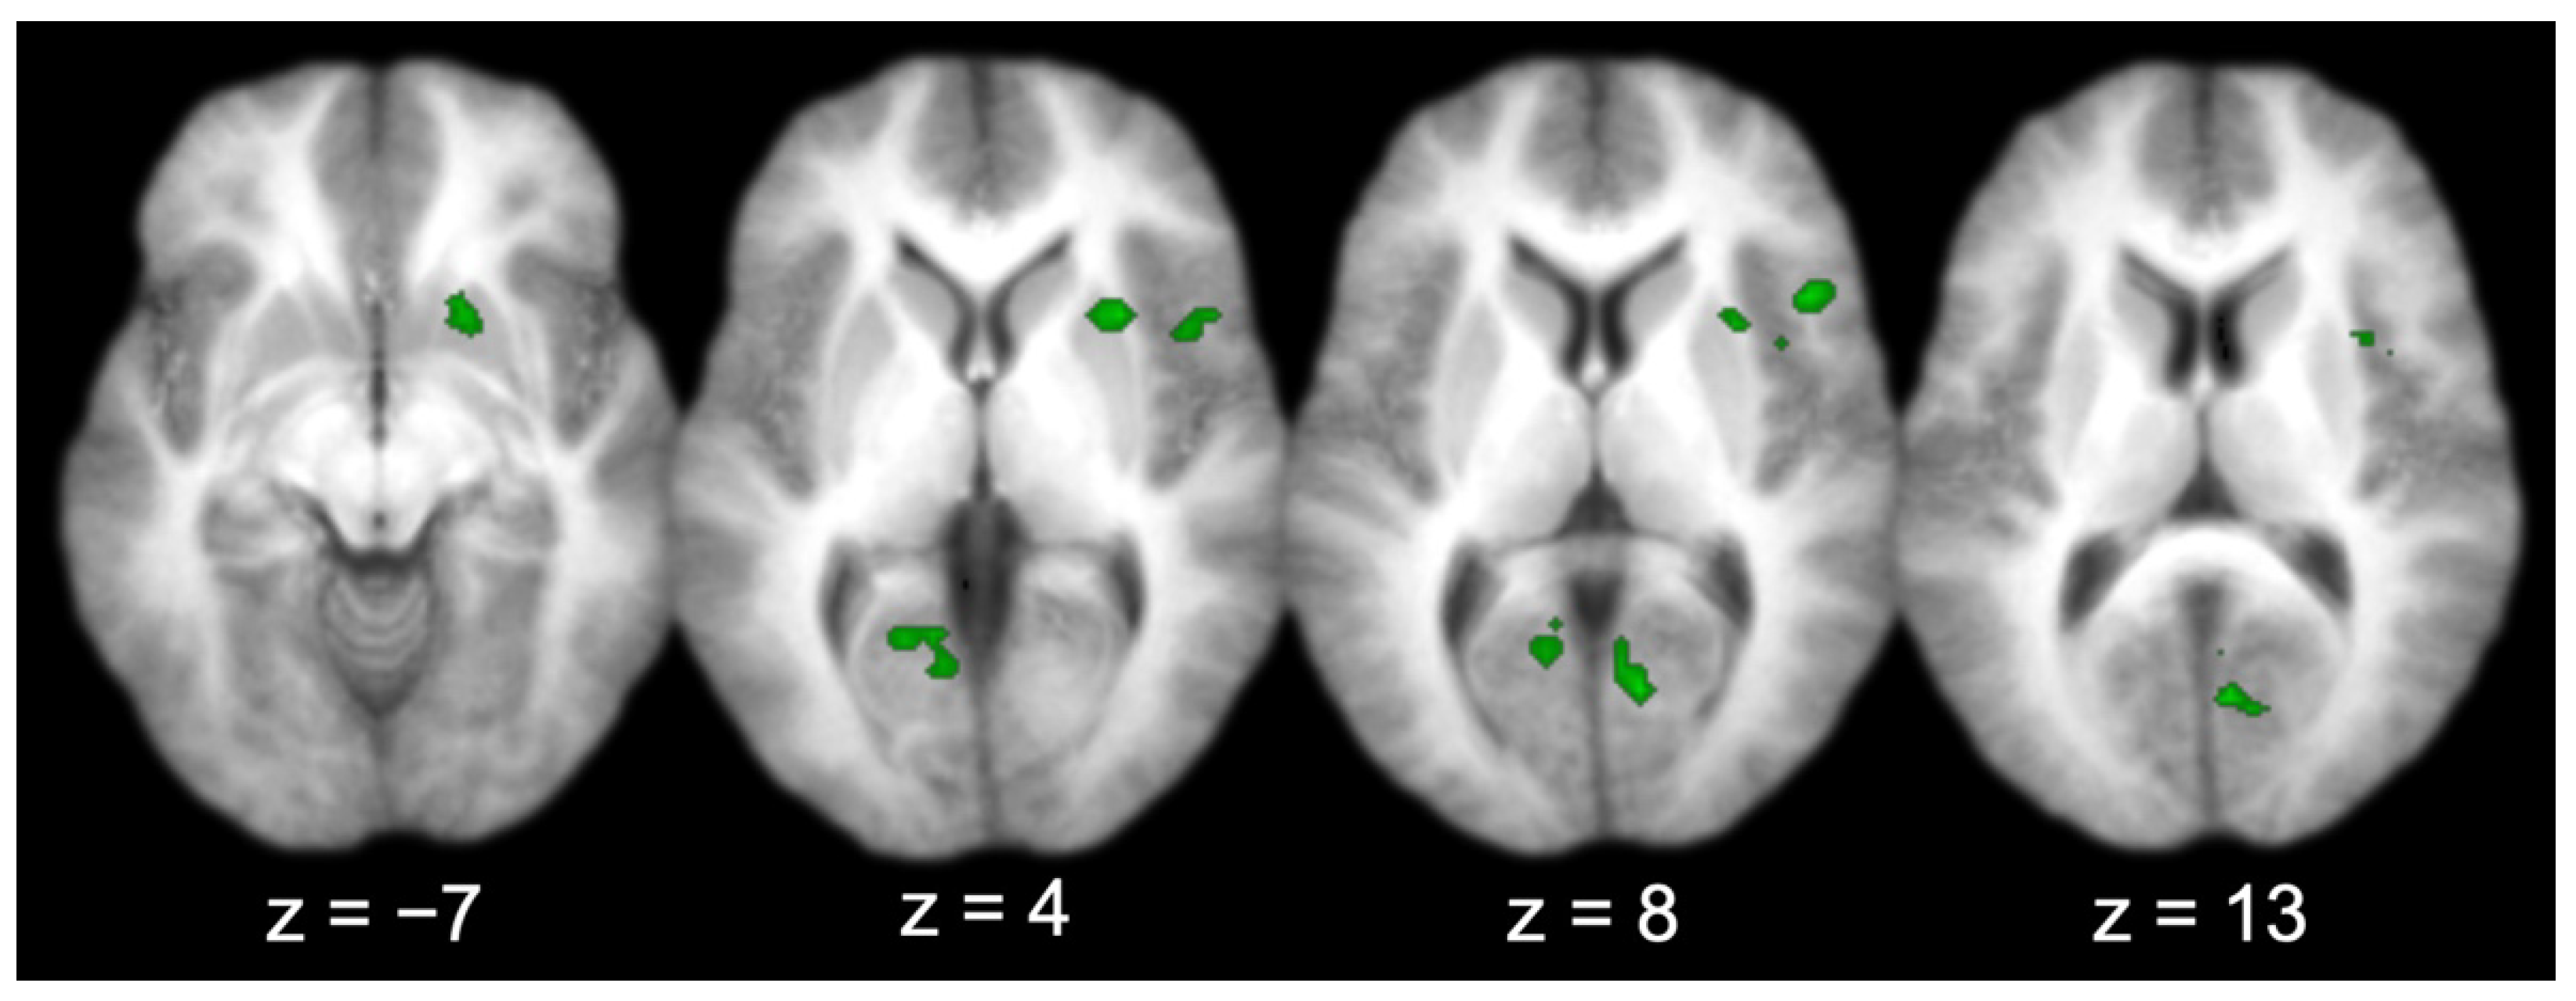

Across all the participants, there were several regions functionally connected to the entorhinal cortex (Table 1 and Figure 4), including the prefrontal cortex (right IFG; middle two panels, top right lateral), visual-processing regions (bilateral V1, bilateral cuneus, and left lingual gyrus; right three panels, bottom), the right insula (right three panels, top right lateral–medial), and the right putamen (left three panels, top right medial). Three activations produced by the group connectivity analysis (i.e., the right IFG/insula, the right V1/bilateral cuneus, and the left V1/lingual gyrus) were selected to test the effect of sex, based on previous findings [5,6,7].

Figure 4.

Entorhinal cortex functional connectivity group results (for all participants; axial slices).